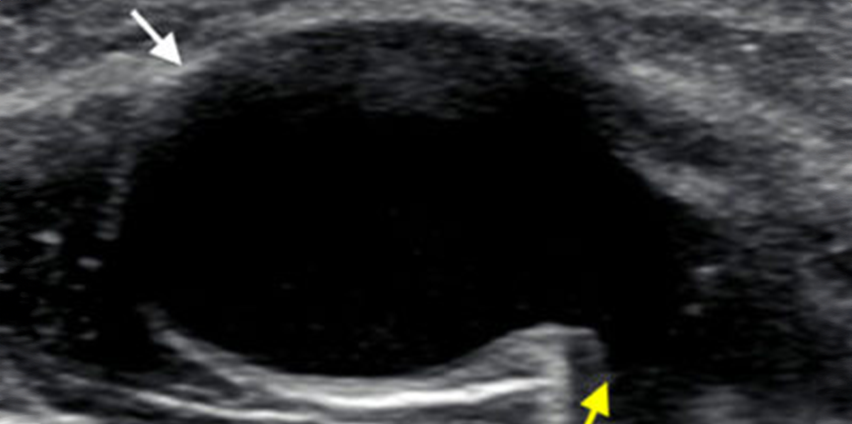

- Image guided therapeutic injections

- Ultrasound guided joint and soft tissue injections (including steroids, high volume injection, dry needling and barbotage)